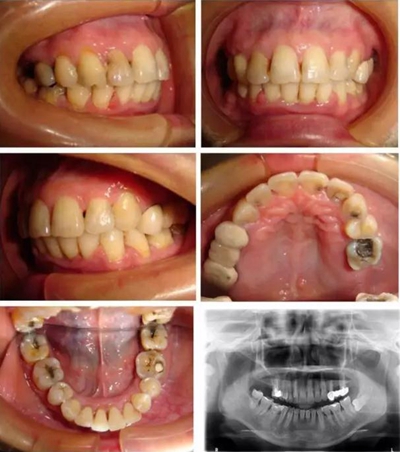

微種植體支抗均保持穩(wěn)定,前牙內(nèi)收明顯,面型得到改善,患者對(duì)矯治效果基本滿意。頭影測量分析顯示:U1-NA角、U1-NA距、L1-NB角、L1-NB距、上唇突度、下唇突度及面型角明顯減小,治療前后差異均具有統(tǒng)計(jì)學(xué)意義(P <0.05),而SNA、SNB、ANB、U6-PP、MP/FH治療前后差異無統(tǒng)計(jì)學(xué)意義(P >0.05)。

▲ 圖4 矯治26個(gè)月后,患者牙(牙合)像、曲面斷層、頭顱側(cè)位片及側(cè)面像